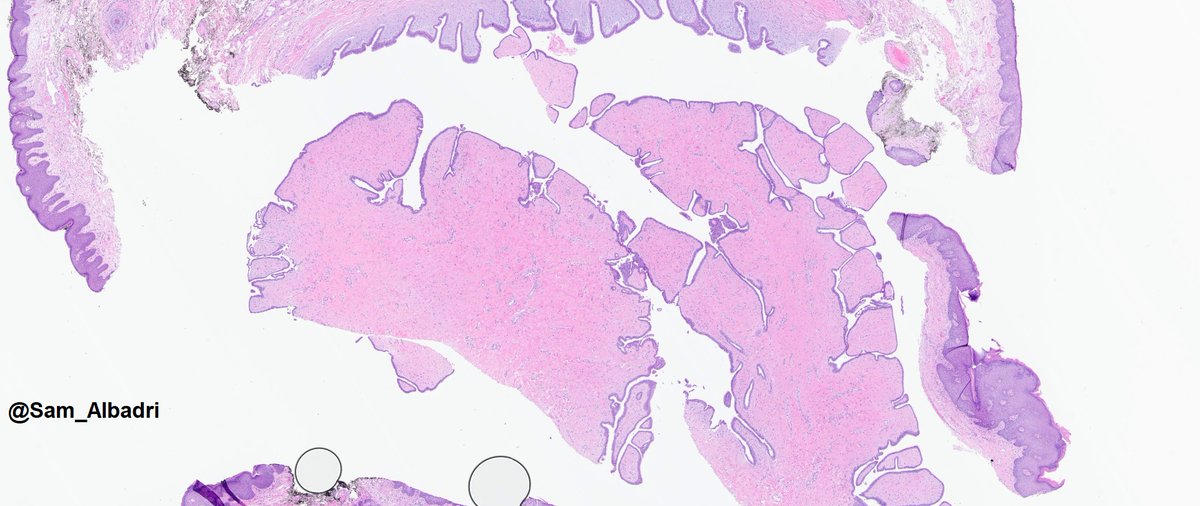

Pulmonary lymphangitic carcinomatosis- Lymphatic vessels occupied by tumor nests around a pulmonary artery. #pulmpath 🫁 #lungcancer

Pulmonary lymphangitic carcinomatosis- Lymphatic vessels occupied by tumor nests around a pulmonary artery.

#pulmpath 🫁 #lungcancer